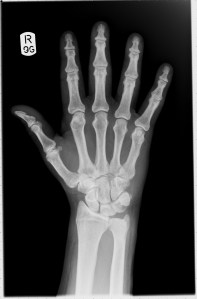

Did you know that you have 27 separate joints in each hand? And eight in each wrist?

Those 35 tiny joints, several of which may be inflamed at any given moment, explains a lot of the pain and discomfort I’ve had in my hands and wrists off and on for the last … well … several years, now. Not to mention the last several months and weeks, when the pain started ramping up and sticking around full-time.